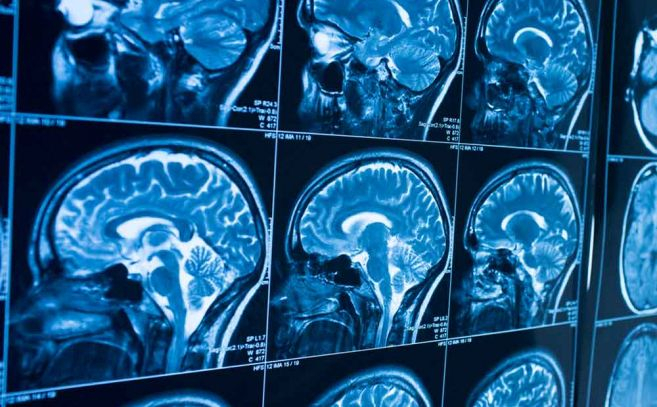

A la luz de estos datos cobra relevancia el trabajo del Dr. Garry P. Nolan, profesor de patología en la Facultad de Medicina de la Universidad de Stanford. Nolan fue contactado por agencias de inteligencia y defensa para analizar resonancias magnéticas de un centenar de individuos –principalmente pilotos, personal de defensa y trabajadores aeroespaciales– que reportaron síntomas neurológicos tras lo que describieron como encuentros cercanos con UAP. En esas imágenes, el investigador encontró patrones indicativos de enfermedad de la materia blanca, un término médico para cicatrices cerebrales similares a las observadas en casos de esclerosis múltiple. Esas zonas blancas, fruto de una respuesta inmunitaria que deja tejido nervioso muerto o cicatrizado, aparecían esparcidas en áreas del cerebro donde la función motora y cognitiva es crítica.

Además, Nolan y su equipo observaron que muchos de estos casos compartían una característica inusual: una mayor conectividad neuronal entre estructuras internas del cerebro –el núcleo caudado y el putamen– que normalmente no se ve en la población general. Esta hiperconectividad plantea preguntas fascinantes: ¿están estas personas genéticamente predispuestas a percibir eventos atípicos o es el propio encuentro lo que desencadena cambios neurológicos? Algunos de los sujetos habían mostrado estas características incluso en estudios previos al supuesto encuentro, lo que sugiere que podría haber una combinación de predisposición neurológica y respuestas fisiológicas únicas en juego.